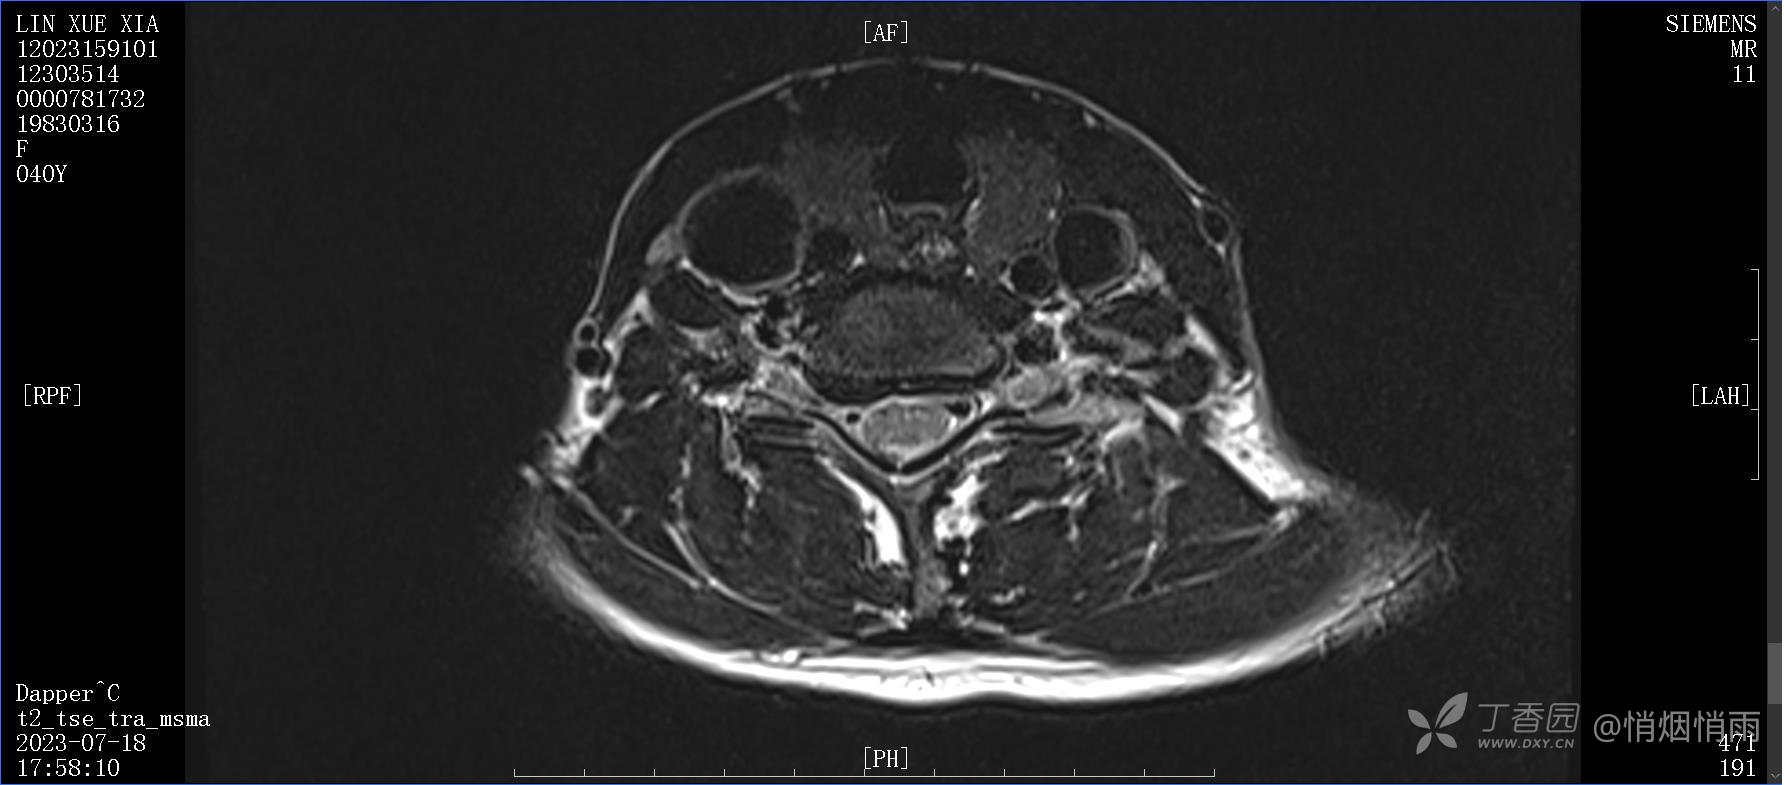

查体:右肩关节局部轻度肿胀,肩胛区压痛明显,痛处不固定,肩关节痛性活动受限,jobe test(+),lift -off test(+),中指、环指感觉较余指减退,余肢端感觉及血运情况可。

目前的诊断,暂时依据辅助检查诊为肩袖损伤,但是患者疼痛的性质和特点,却不是单纯的肩袖损伤所致。考虑过胸廓出口综合征,但是该疾病会出现肩胛区的疼痛吗?(由于考虑到费用的问题,没再进行下一步的检查)带状疱疹会有如此的症状吗?